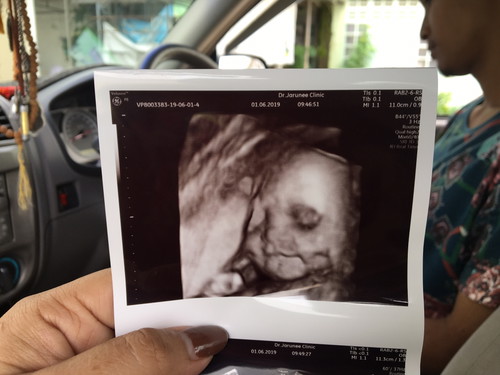

สายสะดือพันคอ2รอบค่ะ

ตั้งครรภ์6เดือนค่ะ. ไปซาวมากคุณหมอบอกว่า สายสะดือพ้นคอ2รอบ. เเม่บ้านไหนเคยเป็นบ้างค่ะ. กลัวมากค่ะ. เเล้วต้องทำอย่างไงค่ะ?

บ้านนี้พึ่งตรวจเจอค่ะ พันคอ2รอบ กังวลไปหมดตอนนี้ปกติก้อยิ่งไม่ค่อยดิ้นอยู่